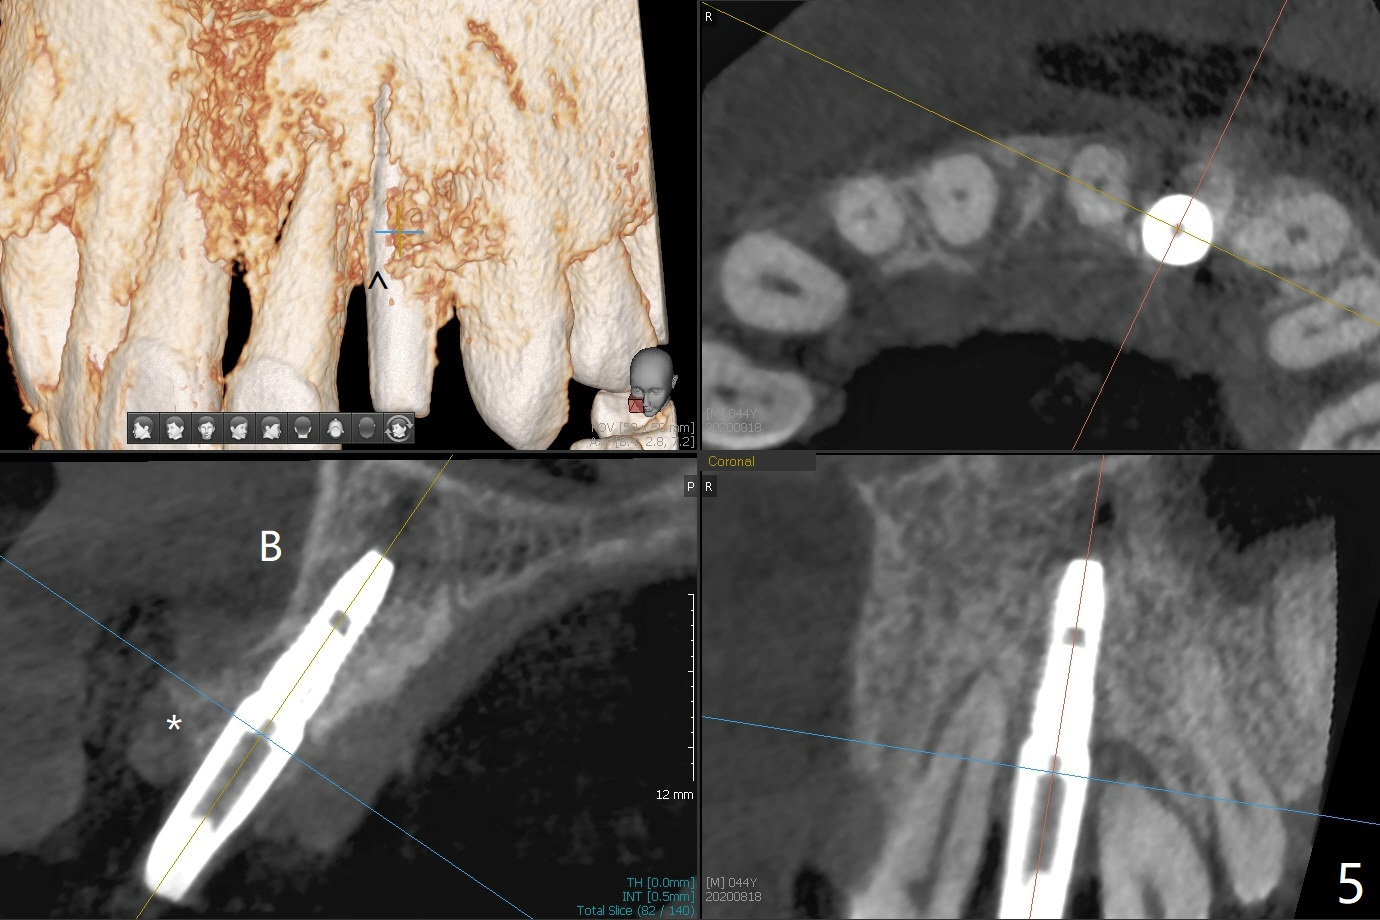

实验结果表明红管抽取上清液形成粘性骨块比白管快。左上二拔除,即刻徒手钻洞(图一),初步植入3.8x11.5毫米植体(图二),调整植体深度,然后放置直径4.5毫米长基台(图三,DIO UF; 牙龈厚度大于6毫米),最后填入大量粘性骨粉(图四,五 *),植体颊侧近中骨粉不足(图五 ^),之后再次充填骨粉。制作即刻修复物,颊侧瘘道和牙槽窝开口放置PRF膜。术后三周临时牙冠松动,取出后者,颊侧空间有两个区域:牙龈和骨粉(图六:白,黑星号)。由于脑部手术,术后接近一年病人回来取模。由于基台长,临时牙冠还没有脱落(图八)。牙龈袖正常(图九:*)。术后一年骨粉仍在植体,基台交界处(图十)。